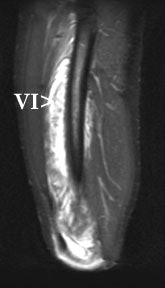

| Coronal ultrasound image of the lateral thigh. Image was obtained using a panoramic field of view. The superficial muscle, the vastus lateralis (VL), shows normal echogenicity throughout. The muscle deep to it, the vastus intermedius (VI), is heterogeneous in echogenicity, consistent with edema. Markers delimit a 16-cm-long region with multiple fluid collections which represents more focal hematoma. |